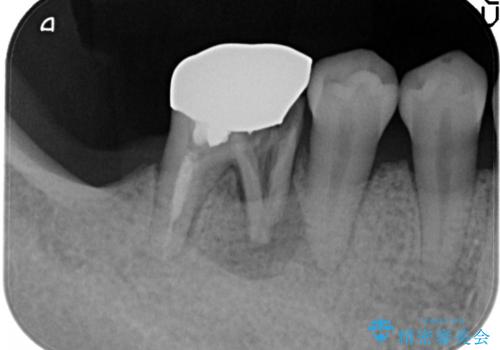

- 奥歯が破折していたため、抜歯を行ったあとインプラントを埋入して咬合回復を行っております。

インプラント埋入時に骨が足りない場合にはインプラント埋入時に骨増生を行います